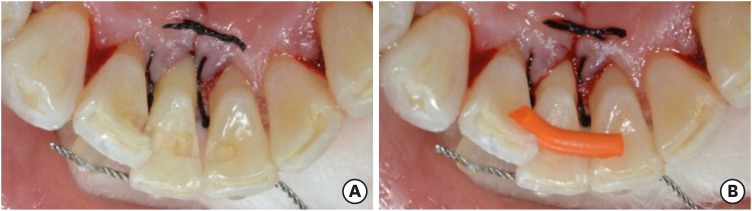

First of all, to mark the gingiva level, a black dot was made on the labial and lingual surfaces of the tooth (Figure 2). Then, the coronal fragment and fractured root were extracted under local anesthesia (Figure 3). An access cavity for the coronal fragment was formed on the lingual surface of the tooth using a high-speed #330 bur (H7.314.008, Komet, Lemgo, Germany). The root canal was enlarged using a Gates-Glidden drill (MANI, Tochigi, Japan). Next, the coronal fragment was soaked in 5% sodium hypochlorite for 5 minutes. The root canal was filled with a resin-modified glass ionomer (Fuji II LC, GC, Tokyo, Japan) and polished using a white stone (Dura-White Stones, Shofu, Kyoto, Japan) and One-gloss (Midi, Shofu) (Figure 4). The coronal fragment was reinserted in the extraction socket and fixed temporarily using G-fix (GC) and a twisted wire (0.0215″ stainless steel wire, American Orthodontics, Sheboygan, WI, USA). The torn gingiva during root fragment removal was ligated with 4-0 black silk (AILEE, Busan, Korea) (Figure 5). Space for a reinforcing fiber was made using a high-speed tapered diamond bur (SF-12, MANI) on the middle of the lingual side from the mesial aspect of tooth #42 to the distal aspect of tooth #31, across tooth #41. The depth of the preparation was approximately 1.0 mm to make adequate space for the fiber and composite resin. The length of the cavity was measured using a Wedjet (Coltene/Whaledent, Alstatten, Switzerland) and Everstick C&B fiber (GC) was cut to that length (Figure 6). A 37% phosphoric acid gel (DenFil Etchant-37, Vericom, Anyang, Korea) was applied to the enamel for 20 seconds, rinsed off, and then gently dried. Singlebond Universal (3M ESPE, St. Paul, MN, USA) was applied to the enamel and dentin, dried gently for 5 seconds, then light-cured for 10 seconds using a LED curing light (G-Light, GC) A thin layer of flowable composite was placed on the preparation site and the fiber was inserted using hand instruments and then light-cured. Composite resin (Filtek Z-350 XT, 3M ESPE) was packed on the fiber and interproximal surface. Because of crowding of tooth #41, resin was packed on the buccal side of the pontic and adjacent teeth to reinforce the connector area. Areas of premature contact or lateral excursion contact on the pontic site were removed during occlusal adjustment. After occlusal adjustment using a diamond finishing bur, the surfaces were polished with One-gloss and an Astro-brush (Ivoclar Vivadent, Schaan, Liechtenstein) (Figure 7). The stiches were removed after 1 week.

Figure 5

Labial view after temporary fixation.

rde-45-e8-g005.jpg